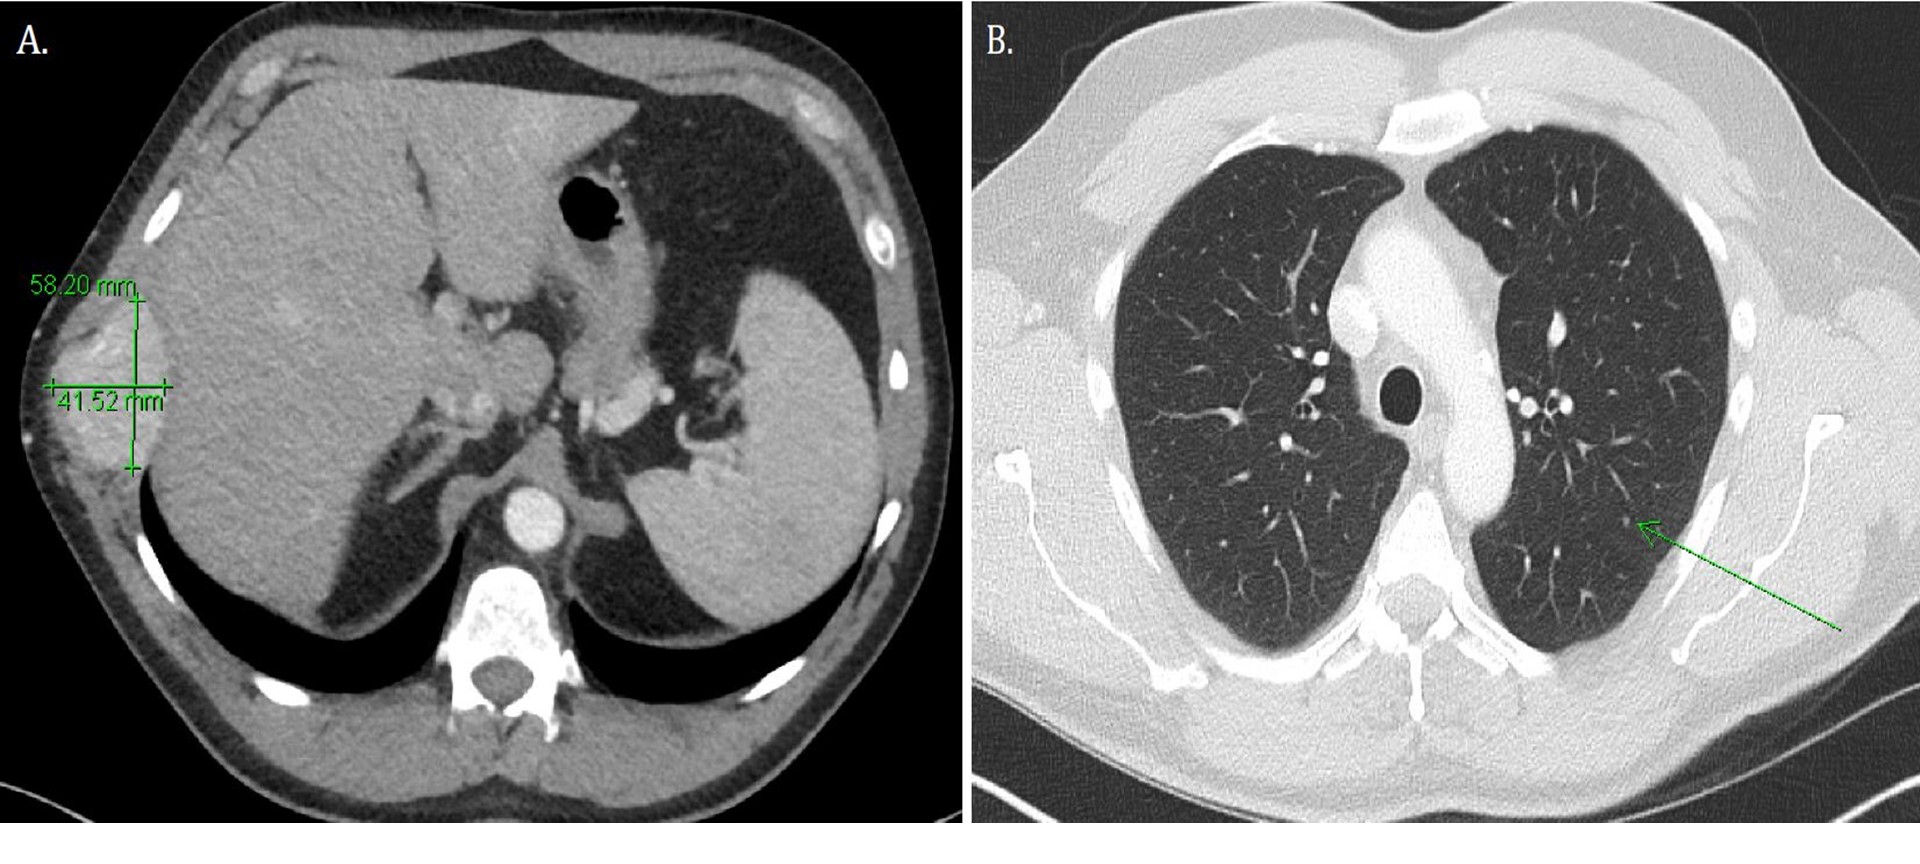

Work-up of the right chest wall mass included a CT chest which demonstrated an expansile destructive right rib lesion measuring 5.8 x 4.1 x 6.5 cm and a nonspecific 3mm pulmonary nodule (Figure 1). A CT-guided biopsy of the chest wall mass was most consistent with clear cell RCC (Figure 3). Subsequent CT of his abdomen demonstrated a 3.9 x 4.2 x 4.0 cm heterogenous exophytic right renal mass (Figure 2). The patient denied gross hematuria, unintentional weight loss, constitutional symptoms, and pain. His physical exam was remarkable for a palpably firm right chest wall mass, and lab data revealed normal serum hemoglobin, absolute neutrophil count, platelets, and calcium. With his excellent performance status and normal lab results he was assigned to the intermediate risk group as per the International Metastatic RCC Database Consortium (IMDC) prognostic model13. Notably, he had mild baseline chronic kidney disease with a serum creatinine of 1.5 and an estimated glomerular filtration rate was 48.2 ml/ min/1.78 m2.